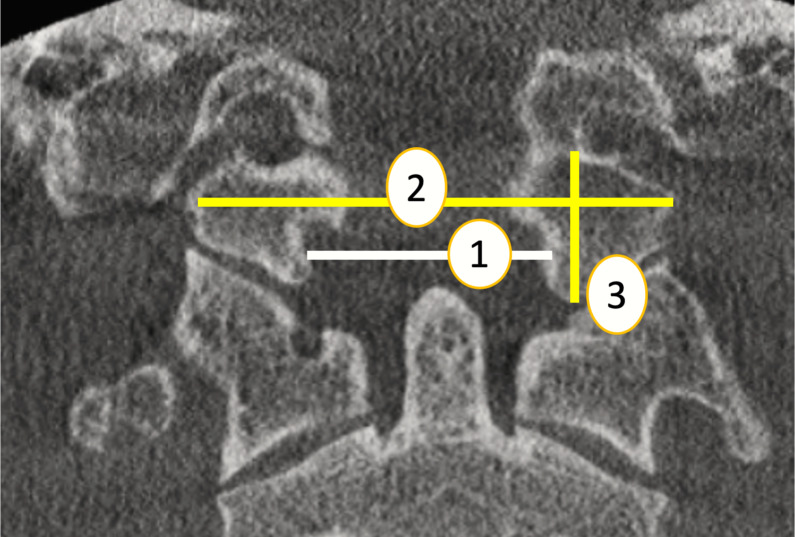

Transverse diameter of foramen magnum (TDFM): The maximum horizontal distance of foramen magnum on axial plane. ref. Marques et al. (2012) (Fig. 1, point 1).

Width of right to left occipital condyle (WOC): The greatest distance from the left occipital condyle to the right occipital condyle on axial plane (ref. Abdel-Karim, Housseini & Hashish, 2015). (Fig. 1, point 2).

The occipital condyle height (right and left) (OCH) was measured on coronal CT images as the length of a line centered in the occipital condyle between the midpoint of its superior articular surface and the midpoint of its inferior articular surface (ref. Abdel-Karim, Housseini & Hashish, 2015) (Fig. 1, point 3).